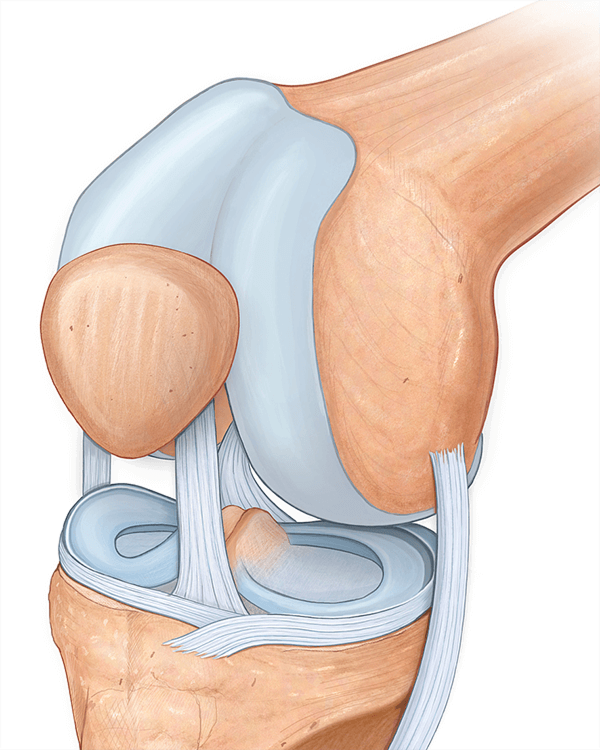

5. Osteoporozning oldini olish

Kollagen suyaklar uchun foydali bo‘lib, osteoporozning oldini olishga yordam beradi. Suyaklardagi organik moddalarning taxminan 70–80% ini kollagen tashkil etadi. Shu sababli suyaklar shakllanish jarayonida skelet tuzilmasini hosil qilish uchun yetarli miqdorda kollagen tolalari sintez qilinishi zarur. Shuning uchun ayrim mutaxassislar kollagen oqsilini “suyak ichidagi suyak” deb atashadi. Kollagen yo‘qolishi yoki yetishmasligi B toifa osteoporoz kasalligiga olib kelishi mumkin.

6. Mushaklarni shakllantirish va mustahkamlash

Kollagen mushaklarni shakllantirish funksiyasiga ega. U mushak massasini oshirishga yordam beradi. Kollagenni kundalik ravishda yetarli miqdorda qabul qilish o‘sish gormoni ajralishini va mushaklarning o‘sishini rag‘batlantiradi. Shuningdek, kollagen mushak kuchini saqlab turishga yordam beradi.